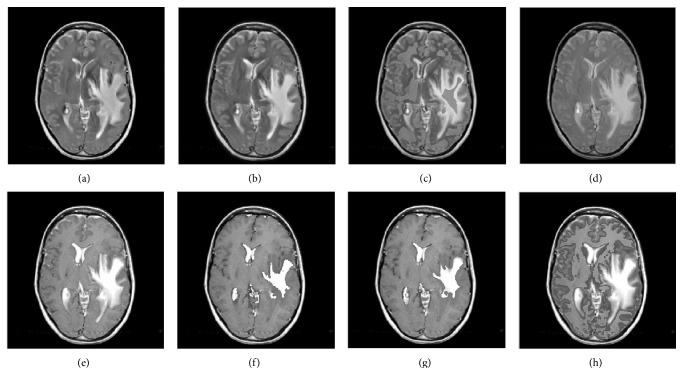

Medical image fusion plays an important role in diagnosis and treatment of diseases such as image-guided radiotherapy and surgery. Although numerous medical image fusion methods have been proposed, most of these approaches are sensitive to the noise and usually lead to fusion image distortion, and image information loss. Furthermore, they lack universality when dealing with different kinds of medical images. In this paper, we propose a new medical image fusion to overcome the aforementioned issues of the existing methods. It is achieved by combining with rolling guidance filter (RGF) and spiking cortical model (SCM). Firstly, saliency of medical images can be captured by RGF. Secondly, a self-adaptive threshold of SCM is gained by utilizing the mean and variance of the source images. Finally, fused image can be gotten by SCM motivated by RGF coefficients. Experimental results show that the proposed method is superior to other current popular ones in both subjectively visual performance and objective criteria.

医学图像融合在诸如图像引导放疗和手术等疾病的诊断和治疗中发挥着重要作用。尽管已经提出了许多医学图像融合方法,但这些方法大多对噪声敏感,通常会导致融合图像失真和图像信息丢失。此外,它们在处理不同类型的医学图像时缺乏通用性。在本文中,我们提出了一种新的医学图像融合方法来克服现有方法的上述问题。它是通过结合滚动引导滤波器(RGF)和脉冲皮层模型(SCM)实现的。首先,RGF可以捕捉医学图像的显著性。其次,利用源图像的均值和方差获得SCM的自适应阈值。最后,由RGF系数驱动的SCM可以得到融合图像。实验结果表明,该方法在主观视觉性能和客观标准方面均优于其他当前流行的方法。